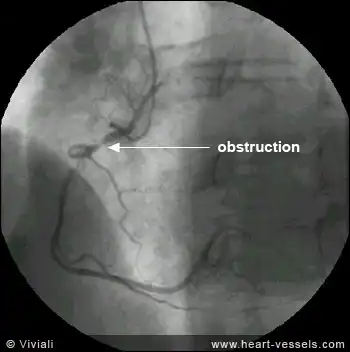

В идеале больной должен доставляться в кардихирургическое отделение, где в первые же часы от появления болей ему выполнят аортокоронарографию (специальный ренген-снимок с контрастированными коронарными артерии, на котором четко видно, какая именно веточка коронарных сосудов заблокирована), и при необходимости – баллонную ангиоплатику и/или стентирование коронарной артерии или аорто-коронарное шунтирование.

На снимке (коронарография) четко определяется участок обструкции коронарной артерии.